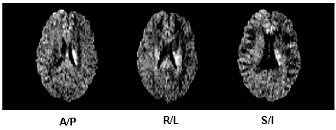

Figure 8. Individual gradient directions: A/P, R/L, and S/I

Figure 9. Combined image from three orthogonal gradient directions